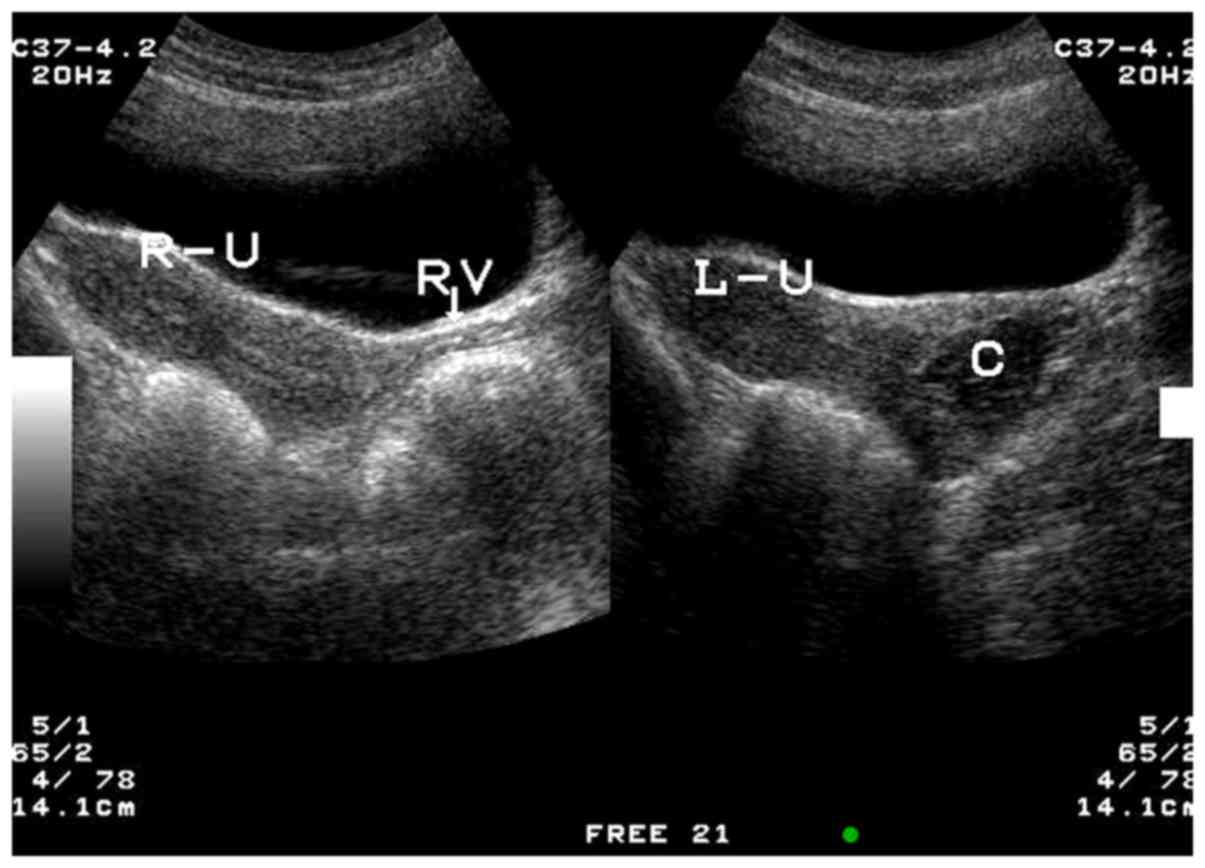

Out of the 15 patients with type I CVOS, there were 9 patients with right oblique septum and 6 patients with left oblique septum (Figs. 2–4). Among the 4 patients with type II CVOS, 3 patients had oblique septum on the right side and another on the left of the vagina (Fig. 5). In the 2 patients with type III CVOS, the septum was on the right side of the vagina (Fig. 6). Patients with types II (n=4) and III (n=2) CVOS exhibited an anechoic vaginal mass with an irregular shape and thickening wall, which was consistent with pathological findings.

Figure 5.

Type II congenital vaginal oblique septum syndrome. Sonograms obtained from a 19-year-old female patient in sagittal pelvic planes exhibiting a cystic mass with dense floating echogenic dots behind the left septum vaginal cavity. The right uterus and right vagina (right side of the figure) and left uterus were normal. R-U, right uterus; RV, right vagina; L-U, left uterus; C, left septum vaginal cavity.